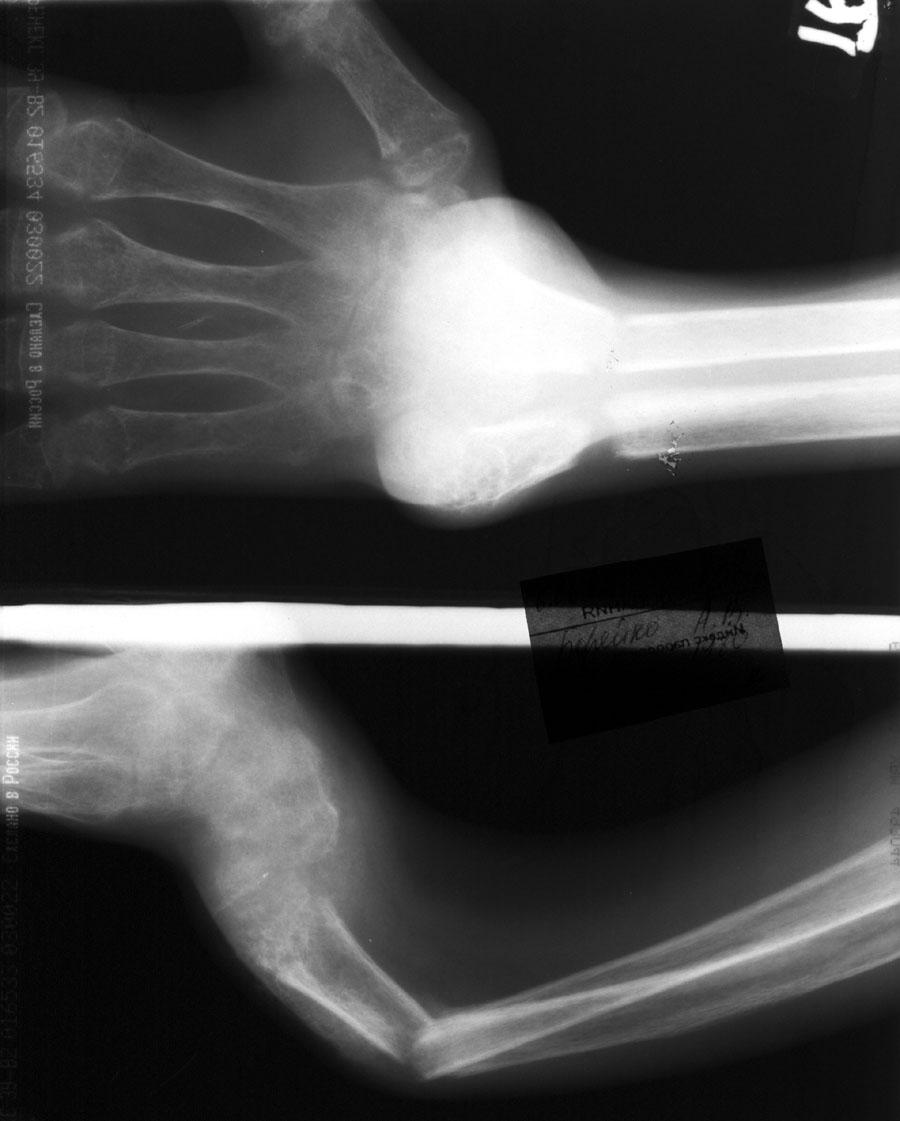

Выписка из амбулаторной карты пациента, 1980 г.р.Находится под наблюдением в поликлинике КНЦ РАН. Состоит на "Д" учёте по заболеваниям:Ювенильный идиопатический генерализованный остеопороз. Деформация грудной клетки за счёт множественных переломов грудины, рёбер. S-образный кифосколиоз грудного отдела позвоночника.Синдром гипофосфатемии неясного генеза. ВСД по кардиальному типу.Инвалид 1-й группы с детства. Последние 4 года не может передвигаться, возникают патологические переломы. Живёт в семье, материально-бытовые условия удовлетворительные.За последние 2 года состояние значительно ухудшилось - усилилась общая слабость, участились патологические переломы, которые не срастаются. Постоянно лежит в постели. Постоянный приём препаратов кальция и диеты с повышенным содержанием кальция, фосфора и белка эффекта не дают. С 11.07.2002 по 30.07.2002 г. лечился в травматологическом отделении АЦГБ с переломом костей правого предплечья со смещением. С 24.08.2002 по 08.09.2002 г. лечился в терапевтическом отделении по поводу острого бронхита с бронхоспастическим компонентом.На сегодняшний день статус. Состояние относительно удовлетворительное. В сознании. Положение вынужденное: сидя в инвалидном кресле, сам встать на ноги и передвигаться не может, туалет только с помощью родственников. Бледный, астеничный. Выраженная деформация грудной клетки, выраженный кифоз и сколиоз грудного отдела позвоночника. Экскурсия грудной клетки ограничена. Участие в акте дыхания вспомогательных межрёберных мышц. Пальпация грудной клетки безболезненна. Деформация всех крупных и мелких суставов за счёт увеличенных эпифизов. Деформация длинных трубчатых костей, мышцы рук и ног атрофичны. Температура - 36,8, ЧД - 29 в минуту. Дыхание жёсткое, проводится во все отделы. Слева от угла лопатки и в аксиллярной области влажные мелкопузырчатые хрипы, в межлопаточной области с обеих сторон свистящие хрипы. Пульс 90 ударов в минуту, ритмичный, симмитричный, слабого наполнения и напряжения. АД 120\80 мм рт. ст. Границы относительной сердечной тупости не расширены. Тоны сердца громкие, ритм правильный. Язык влажный, блестит. Живот при пальпации мягкий, не вздут, симметричный, участвует в акте дыхания, безболезненный. Печень по краю рёберной дуги. Стул регулярный, оформлен, без патологических примесей. Мочеиспускание свободное, безболезненное. Симптом Пастернацкого отрицателен с обеих сторон. Отёков нет.Анализ крови общий 26.08.2002: Hb-146 г\л, Эр.-4,8, ЦП-0,91, Лейк.-6,4, п.-4, с.-45, э.-5, м.-11, СОЭ-4 мм\ч.Анализ мочи общий 26.08.2002: Уд. вес-1025, белок-0,01, сахар-нет, лейк.-0-1 в поле зр., слизь+++, бактерии+.Анализ крови биохимический 26.08.2002: глюкоза-4,9, АЛТ-0,3, АСТ-0,5, биллирубин-11,9, креатинин-44,2, мочевина-3,8, СРБ (+).Анализ крови на микрореакцию - отрицательный.Флюрограмма за 2002: Резко выраженная деформация грудной клетки за счёт множественных переломов рёбер, грудины. Инфильтративных теней в лёгких не определяется. По сравнению с предыдущим исследованием от 01.12.2000 г. - ухудшение: нарастают деформация грудной клетки и позвоночника.ЭКГ за 2002 год: Синусовая тахикардия с ЧСС 88 в минуту. Отклонение ЭОС вправо. Признаки нарушения процессов реполяризации миокарда задней стенки левого желудочка. Повидимому, изменения ЭКГ обусловлены позиционными изменениями, возможно астеничным телосложением.Дополнительные методы исследования.Рентген правого предплечья (17.10.2002): Металлоостеосинтез по поводу перелома обеих костей правого предплечья в н\з: признаки репарации практически не определяются, сохраняется диастаз между отломками.Рентген правого предплечья (24.04.2003): Металлоостеосинтез по поводу перелома обеих костей правого предплечья в н\з: признаки репарации отсутствуют, формируются ложные суставы. Резко выраженный остеопороз.Рентген правого бедра (18.02.2003): Несросшийся перелом правого бедра на границе с\з и н\з со смещением отломков под углом открытым кнутри. Формирующийся ложный сустав. Выраженный остеопороз костей.Рентген правого бедра (24.04.2003): Угловое смещение отломков правого бедра увеличилось. Признаки репарации крайне вялые: по наружному краю отломков формируются замыкательные пластинки - ложный сустав. Выраженный остеопороз.

3. До 12 лет жалоб не предъявлял, занимался спортом (хоккей). Rg-обследования скелета не проводилось. Первый перелом в 10 летнем возрасте - перелом основной фаланги 1-го пальца правой кисти, консолидация в обычные сроки, однако на Rg отмечена "сетчетость" структуры диафизов, - остеопороз в лёгкой степени. Следующий перелом в 11 летнем возрасте 2-я пястная правой кисти, консолидация в обычные сроки, также отмечена остеопорозность тканей. С 12 летнего возраста стал отмечать умеренную боль и усталость в левой подколенной области. В дальнейшем, присоединилась быстрая утомляемость. Выраженного болевого синдрома не отмечал, затруднения в передвижениях и самообслуживании связывает с усталостью во всех конечностях и быстро наступающей общей утомляемостью. Деформация позвоночника по типу кифосколиоза и деформация крупных суставов отмечается с 15-16 летнего возраста. С 18 летнего возраста самостоятельно практически не передвигается. Патологические, несростающиеся переломы получены в 21 и 22 летнем возрасте. Сейчас пациенту 23 года.